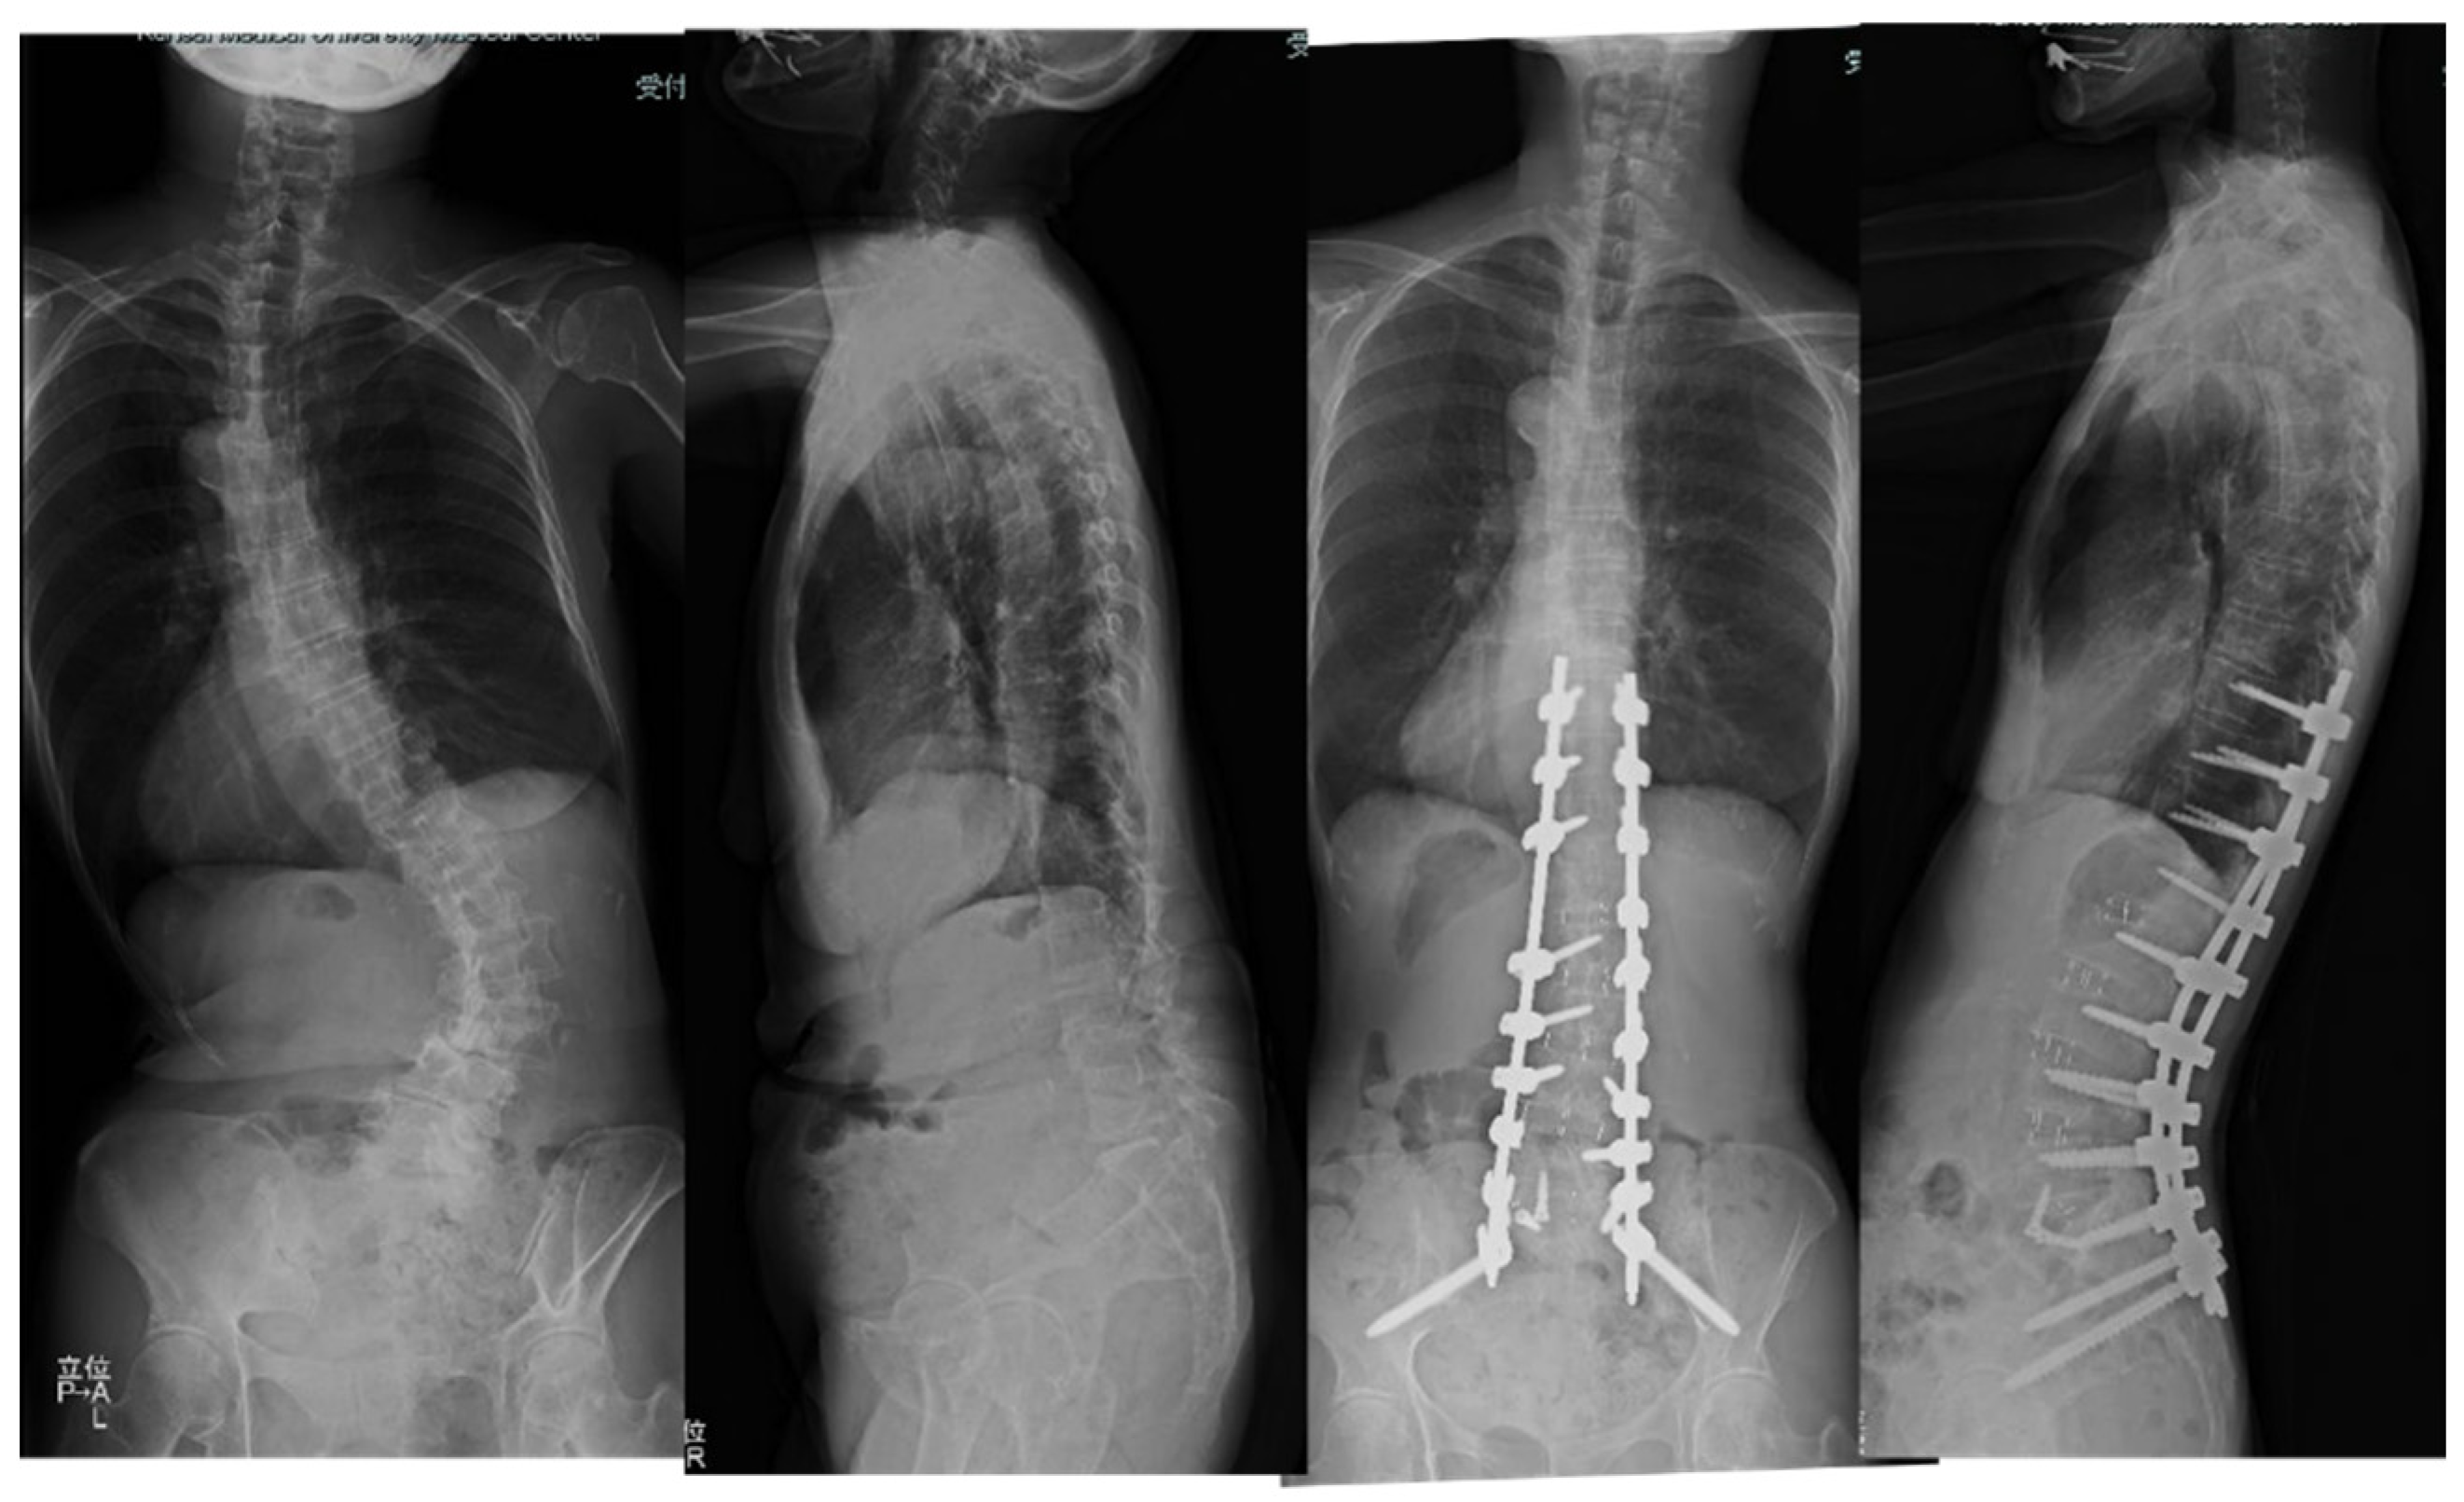

Case 2: 68 years old, female, adult scoliosis

The patient has been suffering from severe low back pain and deformity for several years.

She received cMIS employing OLIF51 with an intraoperative estimated blood loss of 594 ml and operation time of 374 mins totally. The preoperative Cobb angle of 63 degree was corrected to 7 degrees at follow-up. The preoperative PI-LL of 54 degrees was corrected to two degrees at follow-up (Figure 6).

Figure 6. 68 years old female, adult scoliosis The successful cMIS with OLIF51 was performed with a total operation time of 374 mins and estimated blood loss of 594ml. The preoperative Cobb angle of 63 degree was corrected to 7 degrees at follow-up. The preoperative PI-LL of 54 degrees was corrected to two degrees at follow-up.